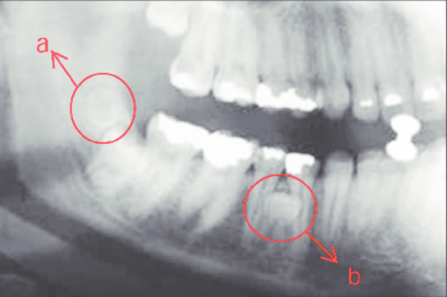

Răng thừa gây nang xương hàm trên Răng thừa mọc vào tiền đình mũi

Răng thừa (a) làm R11 (b) bị kẹt không mọc ra được Tạo khoảng trước phẫu thuật

http://www.dentalnews.com/wp-content/uploads/2015/10/Maxillary-Central14.jpg =http://www.dentalnews.com/wp-content/uploads/2015/10/Maxillary-Central16.jpg =

Phẫu thuật lấy răng thừa sau 4 tháng tạo khoảng Chỉnh nha kéo R11 ngầm lên

Qúa trình chỉnh nha kéo răng cửa mọc ngầm hoàn tất

Hình 5: Minh họa phẫu thuật lấy răng thừa kết hợp với chỉnh nha ở một bé trai 9 tuổi